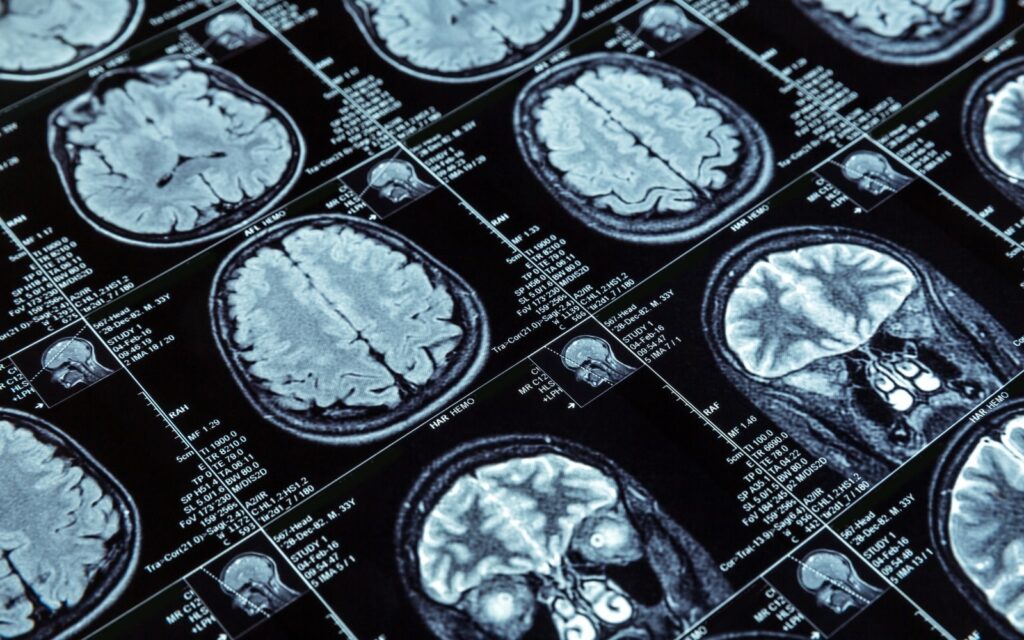

Introducing Perseus, a groundbreaking mobile application powered by edge AI that transforms medical image analysis for healthcare professionals. By leveraging the power of your smartphone or tablet, Perseus allows you to analyze medical images, such as X-rays, CT scans, and ultrasounds, directly at the point of care. This facilitates faster diagnoses, more informed treatment decisions, and ultimately, improved patient outcomes.

Utilize the power of AI algorithms trained on vast medical image datasets. Perseus assists you in identifying potential abnormalities and prioritizing critical cases.

Analyze medical images directly on your mobile device using edge AI processing. Perseus eliminates the need for time-consuming uploads and downloads, allowing for immediate insights.

Gain valuable insights from AI’s image analysis capabilities, leading to more informed diagnoses and improved patient care.